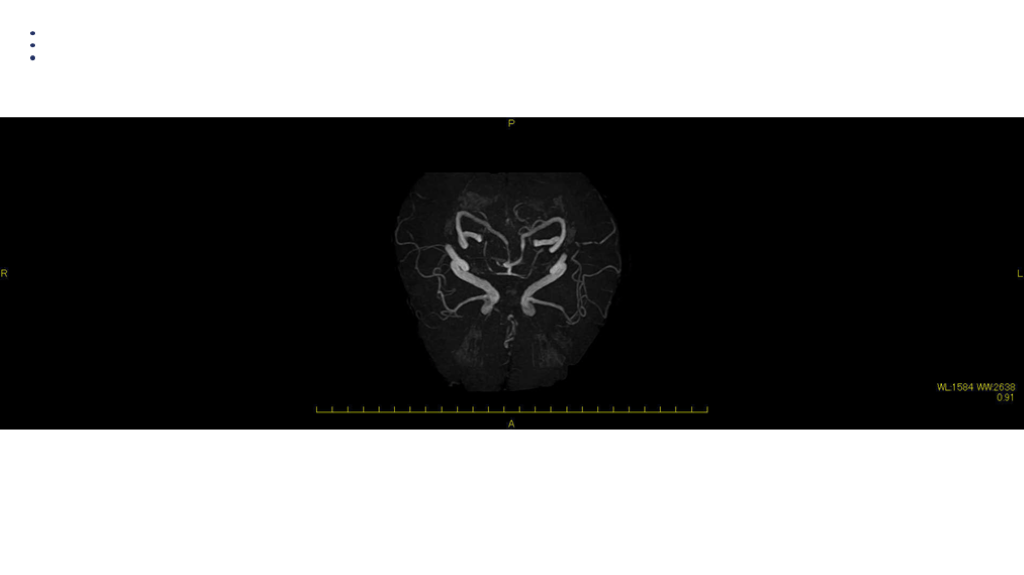

#35.

MRA DAY2